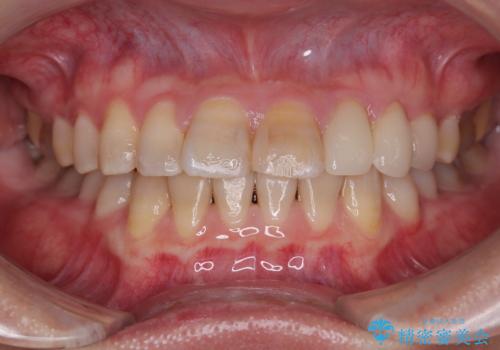

- 詰め物が欠けてしまい、虫歯かもしれないから診てほしいとのことで来院された患者様です。

精査の結果、詰め物の下に虫歯が大きく広がっているのがわかりました。